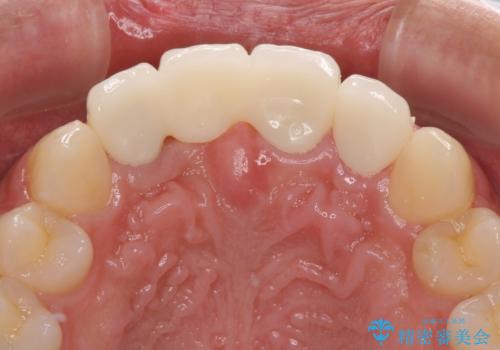

転んでぶつけて抜歯 前歯のオールセラミックブリッジ

- 酒席の後に転倒して前歯を損傷し、応急処置のみを受けてきたとのことで来院された患者様です。

損傷がひどく、前歯4本と広範囲であったため、症状やレントゲン写真、検査結果が一致せず、定期的に経過を見ながら診断していくこととしました。

右側前歯は歯根が短くなり、パンチング状に歯根に透過像が認められたため、予後不良と判断し抜歯することとしました。

当初のレントゲン写真では根尖部に骨透過像が認められた両サイドの2歯は、歯髄の正常な反応が認められたためそのまま保存し、左側前歯は歯髄が失活していたため根管治療を行うこととしました。

抜歯後の欠損部はブリッジにて補綴治療を行うこととしました。